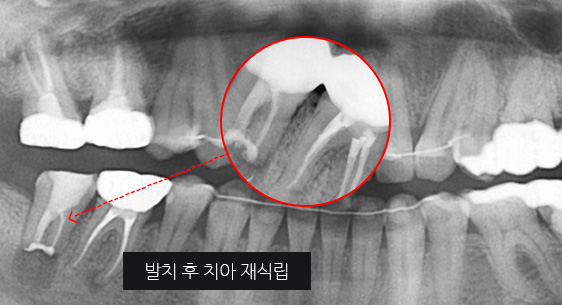

심한 염증으로 치조골이 광범위하게 소실, 아래쪽 신경관이 가까이 있어 치근단수술이 불가능한 상태, 타 병원에서 임플란트 진단을 받았지만, 고운미소치과에서 치아를 발치하고 뿌리 쪽 염증을 제거한 후 발치한 치아를 다시 심는 치아재식술을 시행하였습니다.

기존 신경치료 부위에 염증과 치조골이 소실되고 있는 상태

치아를 발치하고 염증을 제거, MTA로 충전하고 치아를 다시 심음.

(난이도 최상)